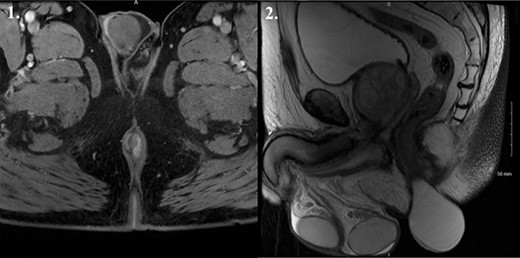

A 69-year-old male presented to his primary care physician with an 8-year history of a slow-growing large mass protruding from the right anal verge. The patient’s past medical history included a previous basal cell carcinoma, coronary artery disease, atrial fibrillation and diverticular disease. The patient had previously undergone colonoscopic investigation of diverticulosis and underwent polypectomy of the three colonic and one rectal tubular adenoma with low-grade dysplasia a year before. There was no past medical history of trauma to the perineal region or previous perineal procedures. On assessment of the patient at the colorectal unit, the mass originated from the skin of the anal verge and was not involving the anal canal. It was cylindrical in shape, was soft and fluctuant with no irregularities and did not display any overlying cutaneous features. Magnetic resonance imaging (MRI) was undertaken and demonstrated a thin-walled homogenous cystic structure arising in the intersphincteric plane measuring 7 cm × 5 cm × 5 cm (Fig. 1). The cyst was well defined with no invasive features and demonstrated high signal on T2-weighted imaging suggestive of a fluid-filled structure.

MRI T2 weighted imaging suggestive of a 7 cm × 5 cm × 5 cm fluid-filled structure arising in the intersphincteric plane. 1. Coronal view. 2. Sagittal view.